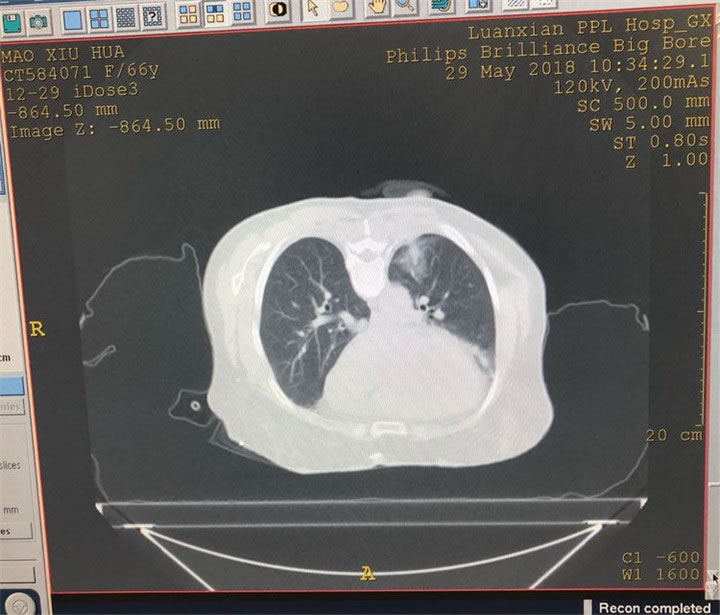

用直徑模式消融14分鐘后影像

消融效果滿意,無(wú)氣胸、無(wú)出血。